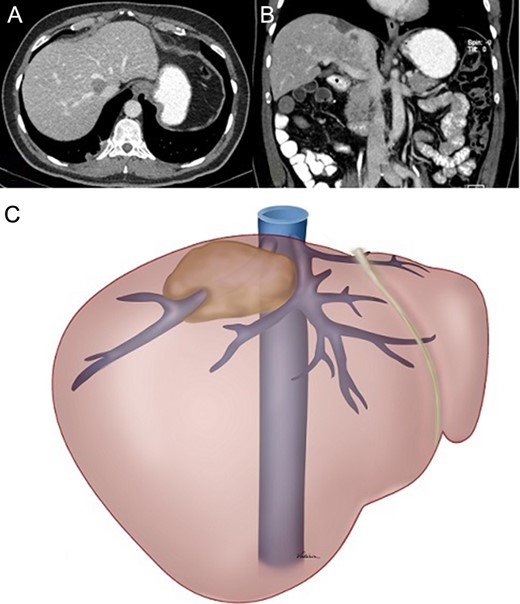

One last 3-minute Pringle manoeuvre was performed. A venotomy was performed in the right hepatic vein on its skeletonized section. The constrained section of the graft was introduced ~2 cm inside the vein and the deployment line was pulled (Fig. 4).

The right hepatic vein was transected and the specimen retracted. A 19-Fr round Blake drain was placed (Fig. 5). Operative time was 7 hours and estimated blood loss was 100 ml.

Final appearance: (A) intraoperative appearance and (B) schematic drawing.